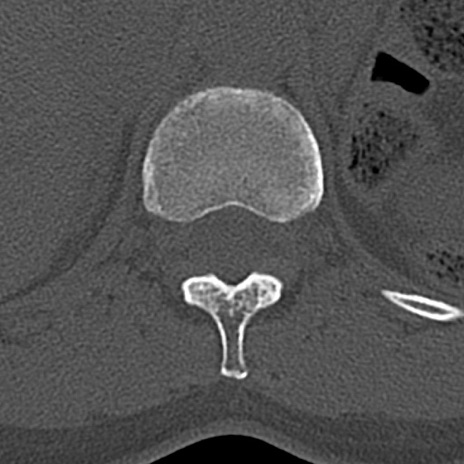

【整形】TIPS症例4 腰椎CT(横断像)

腰椎CT

横断像と矢状断像